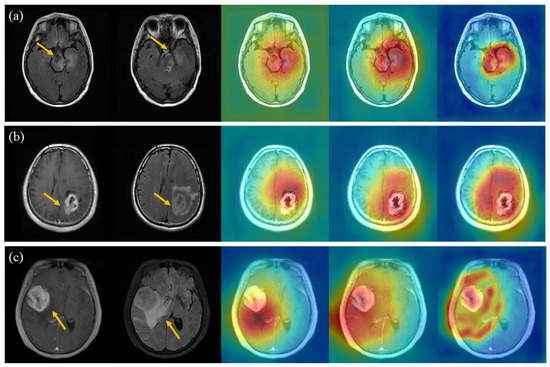

Appendix B. Figures